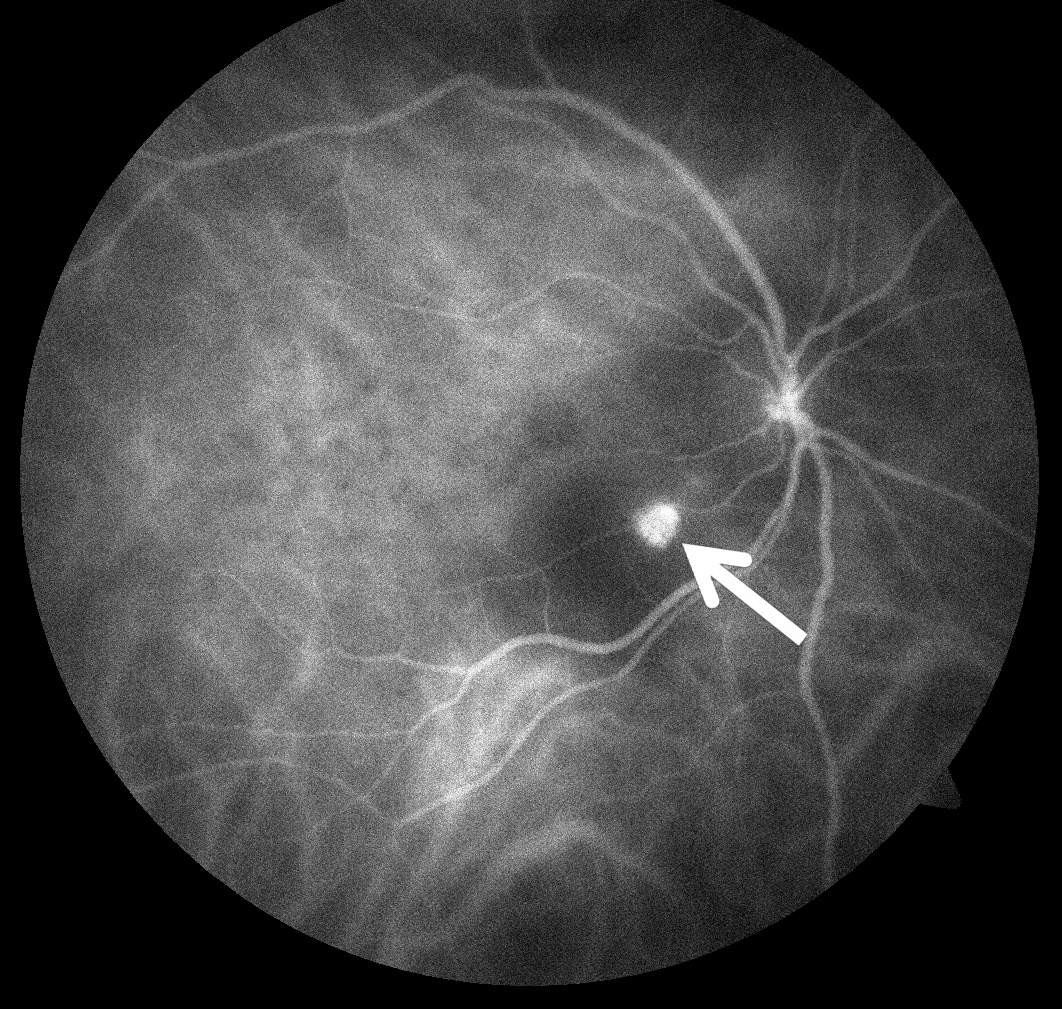

The most important test used to diagnose PCV is a careful dilated eye examination by your retina specialist. In addition, fluorescein and indocyanine green (ICG) angiography may be useful (Figure 2). These 2 tests are able to create detailed images of the retinal and choroidal blood vessels, which can assist your retina specialist in identifying important abnormalities.

Both tests require a special dye to be injected into a vein (usually in the arm or hand) before retinal photographs are taken. Optical coherence tomography (OCT) scanning of the retina is also routinely used to aid in diagnosis of PCV.